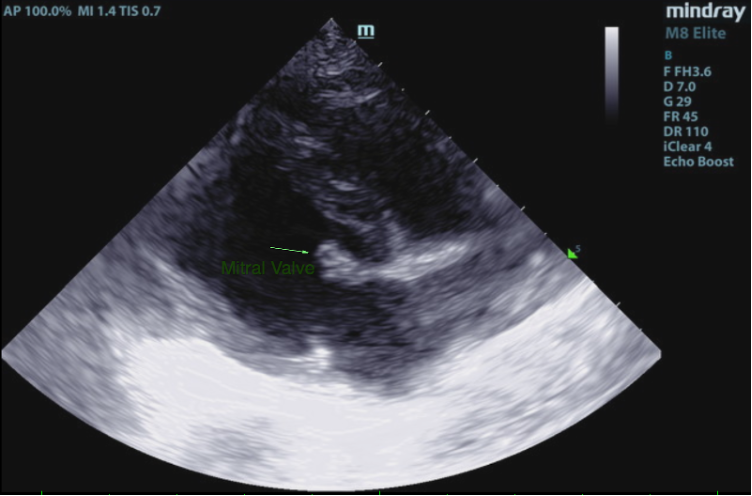

2D, M-mode, color flow, and Doppler imaging is available. The mitral valve is diffusely thickened with prolapse into the left atrial lumen. There is moderate eccentric mitral regurgitation present.

There is moderate left atrial enlargement. There is mild left ventricular dilation. Left ventricular systolic function is adequate. There is normal systolic flow velocity across the aortic valve; no insufficiency. The aortic valve appears normal. Mild right atrial/ventricular enlargement. The tricuspid valve is mildly thickened with moderate tricuspid regurgitation. The tricuspid regurgitant velocity is consistent with moderate to severe pulmonary hypertension (PH). The pulmonary artery is prominent. Normal aortic and pulmonic outflow velocities. No aortic insufficiency (AI) or pulmonary insufficiency (PI). No pericardial/pleural effusion or cardiac masses are seen.